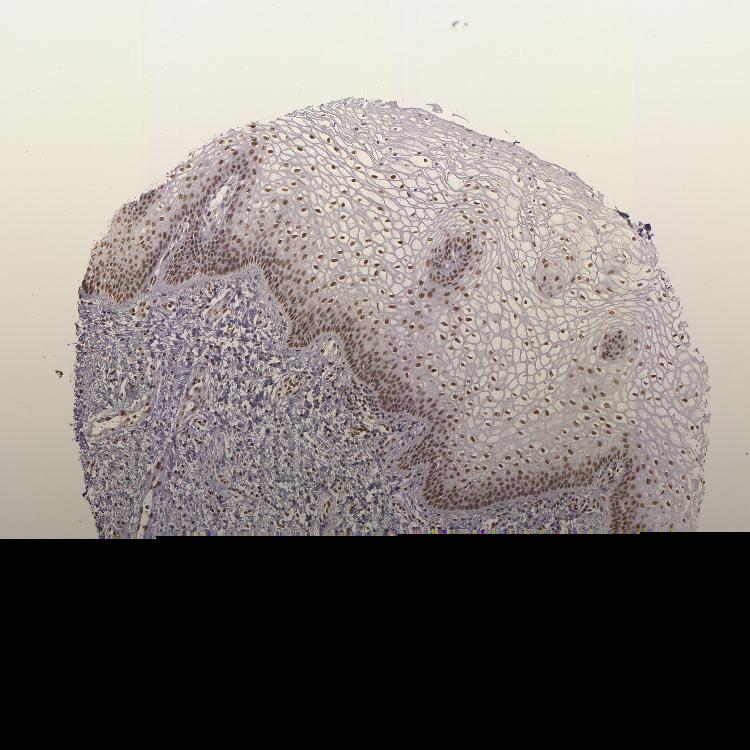

VAGINA - Antibody stainingi

Antibody staining in the annotated cell types in the current human tissue is reported as not detected, low, medium, or high, based on conventional immunohistochemistry profiling in selected tissues. This score is based on the combination of the staining intensity and fraction of stained cells.

Each image is clickable and will lead to virtual microscopy that enables deeper exploration of all samples and also displays staining intensity scores, fraction scores and subcellular localization as well as patient and tissue information for each sample.

Antibody HPA036233Antibody CAB001480

Squamous epithelial cells MediumMedium